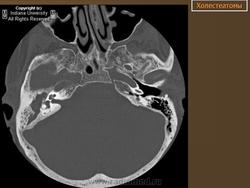

Диагностика холестеатомы представляет определенные трудности. Основными методами выявления холестеатомы последние несколько десятилетий остаются отоскопия (отомикроскопия) и рентгенологические методы (рентгенография в различных укладках и компьютерная томография). Компьютерная томография височных костей позволяет диагностировать холестеатому намного чаще, чем обычная рентгенография, однако степень достоверности данной диагностики остается невысокой, так как плотность холестеатомы практически соответствует плотности грануляционной ткани. Поэтому чувствительность метода КТ в диагностике холестеатомы составляет всего 71% при специфичности 55% [50]. Кроме того, следует учитывать, что указанный метод требует не только дорогостоящего оборудования, но и высококвалифицированных рентгенологов со специальной подготовкой, позволяющей им правильно интерпретировать полученные результаты.

2. Применение компьютерной томографии позволяет повысить степень обнаружения патологического процесса до 90% случаев, однако не позволяет достоверно дифференцировать холестеатому и грануляционную ткань по причине низкой специфичности метода (55%).